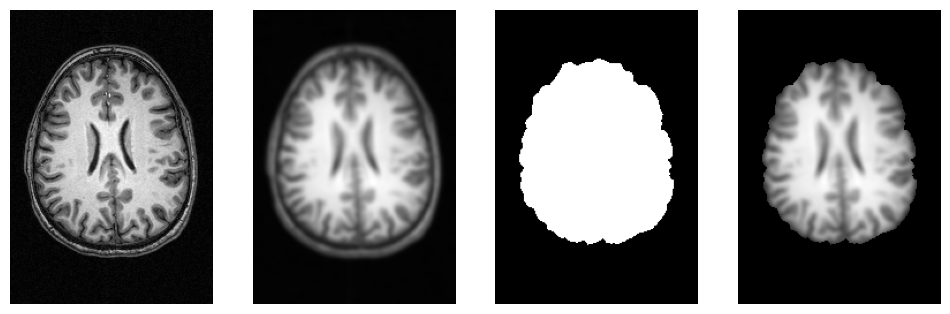

f = plt.figure(figsize=(12, 4))

for i, img in enumerate([input_file,

opj(wf_work_dir, "smoothflow/smooth/sub-01_T1w_smooth.nii.gz"),

opj(wf_work_dir, "smoothflow/skullstrip/sub-01_T1w_brain_mask.nii.gz"),

opj(wf_work_dir, "smoothflow/mask/sub-01_T1w_smooth_masked.nii.gz")]):

f.add_subplot(1, 4, i + 1)

plot_slice(img)